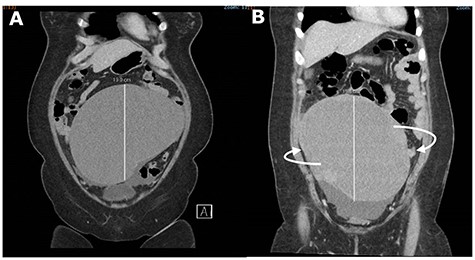

An urgent CT abdomen and pelvis (CTAP) revealed a change in orientation of the large cystic adnexal mass with possible signs of intra-tumoural haemorrhage (Fig. 1). Blood investigations found a haemoglobin level of 9.6 g/dL from a baseline of 12.6 g/dL, leukocytosis of 15.5 × 109/L and lactate was slightly elevated at 1.5 mmol/L.

CT abdomen and pelvis (CTAP) showing acute change in orientation of the right ovarian mass before (A) and after (B) colonoscopy.